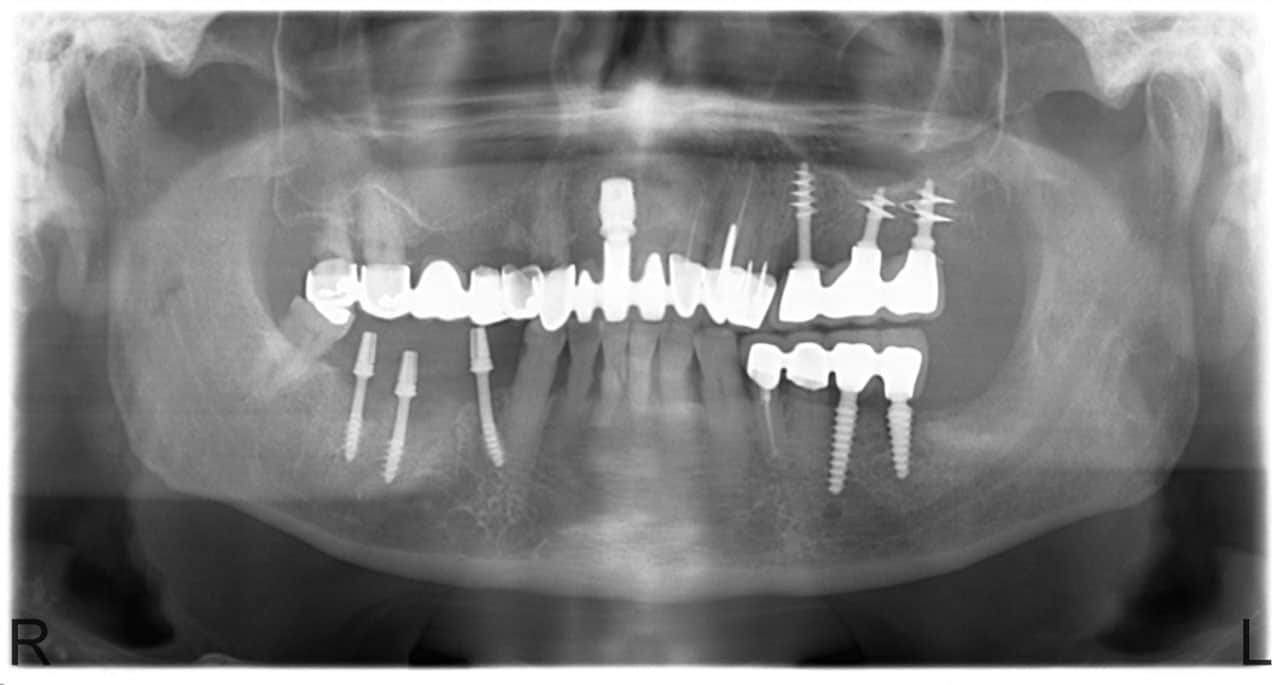

Foghúzás után jöhet az implantátum Budapesten

A fogak elvesztése komoly kihívás elé állíthatja az embert, ezért érdemes minél hamarabb tenni azért, hogy a kellemetlen állapot lehetőleg megszűnjön. Többféle eljárás közül lehet válogatni. Ezek mind arra szolgálnak, hogy rövid időn belül orvosolják a problémát. Az azonnal terhelhető implantátum Budapest térségében egyre inkább terjedő beavatkozást kínál.

Az eredetileg svájci fejlesztésű metódus egyértelműen csúcskategóriás eljárás, ami semmilyen kívánnivalót nem hagy maga után. Az adatok szerint, a siker valószínűsége 98,2 %. Jó hír, hogy az implantátum Budapest még krónikus betegségek esetén is alkalmazható, amikor a hagyományos csontbeültetés nem nyújt segítséget.

Már közvetlenül a foghúzást követően megtörténhet a behelyezés, így a gyógyulás esélye jelentős mértékben javítható, felgyorsítható. Az implantátum Budapest kedvező ár-érték arányon ültethető be, ezért a költséghatékonyság sem fog kifogást jelenteni ezen a téren. A dentalcenterkelemen.hu részletes véleményeket és további hasznos információt lehet találni a végső döntés előtt.